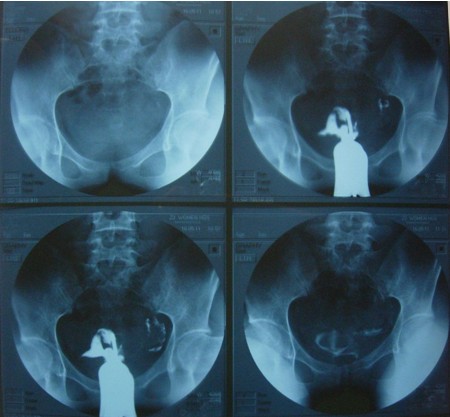

输卵管造影检查过程图片

输卵管造影成影图片

输卵管造影X光图片